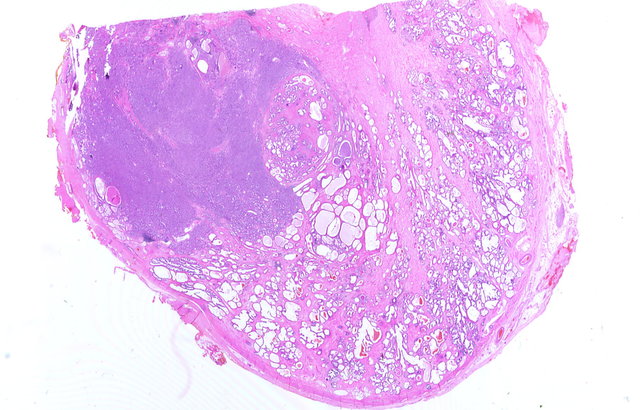

©wikipedia.org/KGH, CC BY-SA 3.0

© wikipedia.org/Alex brollo, CC BY-SA 4.0

© wikipedia.org/Alex brollo, CC BY-SA 3.0